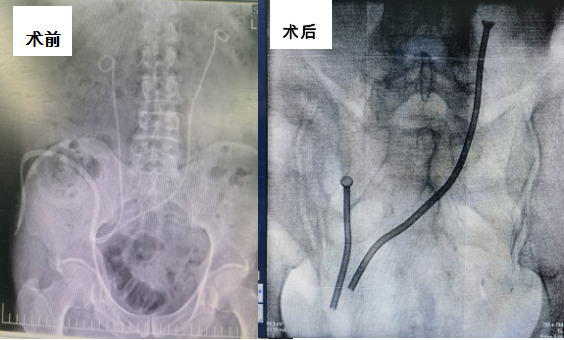

领导和各部门的大力支持下,完成黑料网首例永久性输尿管金属支架植入术。

张军晖主任在术前充分评估,针对术中可能出现的各种情况充分论证、准备,在确保万无一失的情况下于2月19日开展手术。由于患者既往行膀胱癌根治术,吻合口位置特殊,情况复杂,术中反复调试,不断修正,直至确保金属支架能完全覆盖狭窄全段,术后不会发生再狭窄可能。在两位专家的通力合作下手术顺利完成,金属支架位置良好。患者术后引流良好,未出现任何不良反应。